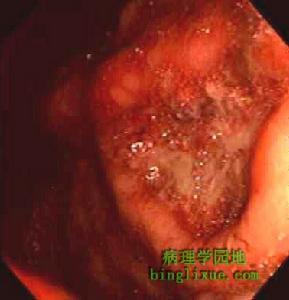

短腸綜合徵(2)胃液高分泌狀態及消化性潰瘍:在人和動物廣泛小腸切除術後胃高分泌狀態是一重要特徵此不僅造成嚴重的消化性潰瘍病,而且對短腸綜合徵吸收功能造成進一步損害,造成黏膜瀰漫性受損,低pH導致胰酶的抑制,減少了脂肪微囊的形成降低腸腔內脂質消化;高分泌狀態的另一作用是大量的胃液加重術後腹瀉,胃液高分泌狀態在廣泛小腸切除術後24h即可出現,隨著時間推移均會造成不同程度損害,對此套用藥物治療可以控制,很少需要外科處理人和狗小腸切除術後血清中胃泌素升高,提示胃高分泌狀態是繼發於此激素的刺激作用或其對胃黏膜的營養作用;另有報導認為小腸切除可能影響胃泌素的分解代謝或影響抑制胃泌素作用的激素的分泌;然而另一些腸切除術後高分泌狀態時血清胃泌物水平並未發現升高,甚至某些病人在腸切除術後表現為低胃酸狀態因此小腸切除術後導致胃高分泌狀態的真正原因尚不清楚。